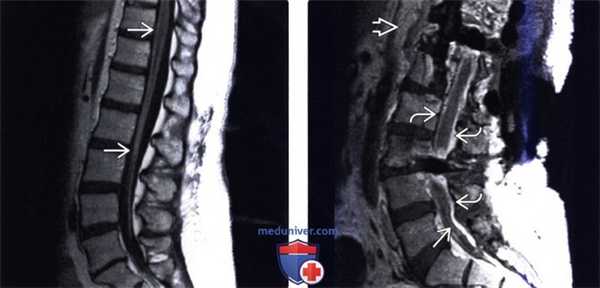

(Слева) Сагиттальный срез, Т1-ВИ с КУ: диффузное патологическое контрастное усиление сигнала конского хвоста и поверхности дистального конца спинного мозга в сочетании со «скученностью» корешков в центральной части дурального мешка. Усиление сигнала мягких мозговых оболочек в данном случае обусловлено гистоплазмозом (эффективно купирован противогрибковыми препаратами).

(Справа) Сагиттальный срез, Т1 -ВИ с КУ: протяженное утолщение твердой мозговой оболочки с контрастным усилением ее сигнала и формированием диффузной флегмоны эпидурального пространства. Видны признаки массивного инфекционного процесса с вовлечением мягких тканей, эпидурального и субарахноидального пространства.